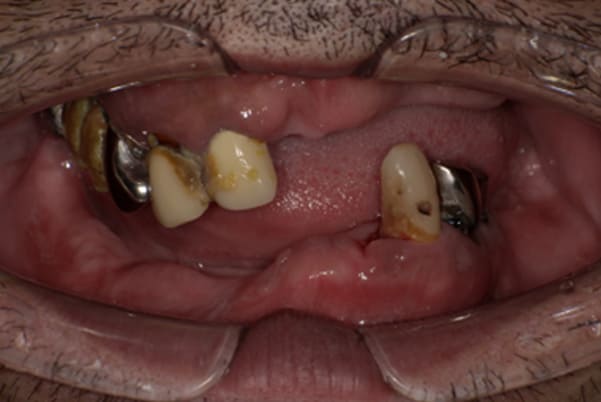

上前歯はブリッジの差し歯により根が折れ炎症を起こしお痛みのある状態でした。

原因は長期使用により下の義歯の歯が削れたことにより、下前歯が上前歯を突き上げ強い力が加わっていたことが根本的な原因と考えられます。

治療前は、奥歯が下がり、かみ合わせが乱れています。適切な入れ歯はそのままのかみ合わせで義歯を作るのではなく治療後のように、前歯から奥歯までのラインが真っすぐ揃った、かみ合わせの面を適切に付与し、よく咬め、残りの歯に負担がかからないかみ合わせとしました。

上顎治療前

-

上顎治療後

根のみの7本は虫歯にもなっており歯肉は腫れあがっています。

残りの歯もレントゲンで重度の歯周炎によりぐらぐらな状態でした。